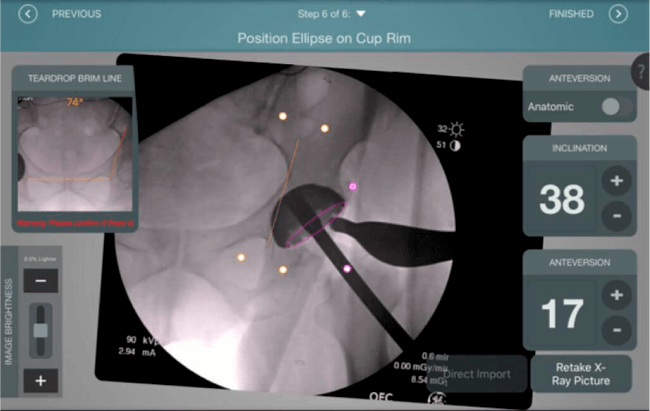

El sistema de navegación digital VELYS HIP NAVIGATION ™ para cirugía de cadera, es una tecnología innovadora y no invasiva diseñada para potencializar la toma de decisiones en tiempo real y basada en datos; aumentando la precisión y mejorando los resultados a corto, mediano y largo plazo para los pacientes.

Inclinación y anteversión de la copa acetabular para una correcta colocación del implante.

Verificación de la posición deseada del implante que potencialmente puede ayudar a reducir la probabilidad de dislocación protésica y aumentar la estabilidad de la articulación.